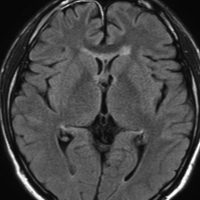

21歳男性で交通事故で偶然発見された両側前頭葉腫瘍です。

ジャーミノーマには好発部位というものがあります,神経下垂体,松果体,大脳基底核などですが,例外的な発生部位もあるので注意です。この例は,浸潤形態が脳室壁に沿う subependymal infiltrationという特徴からジャーミノーマと画像診断できるものです。